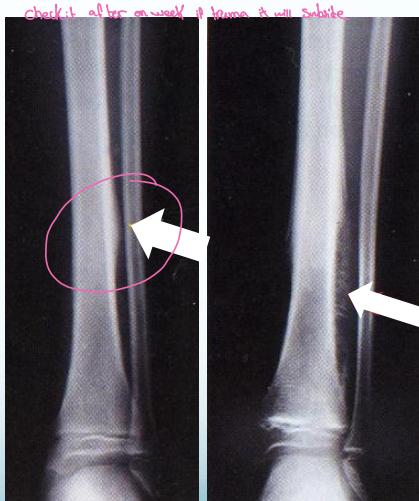

Beware! Malignant Tumors

- Can present as injury

- History of trauma is usual

Case Example:

- 12-year-old girl

- History of trauma

- Mild tenderness

- Periosteal reaction

- Initially diagnosed as injury

- 2 months later, still tender

- Final diagnosis: Ewing’s sarcoma